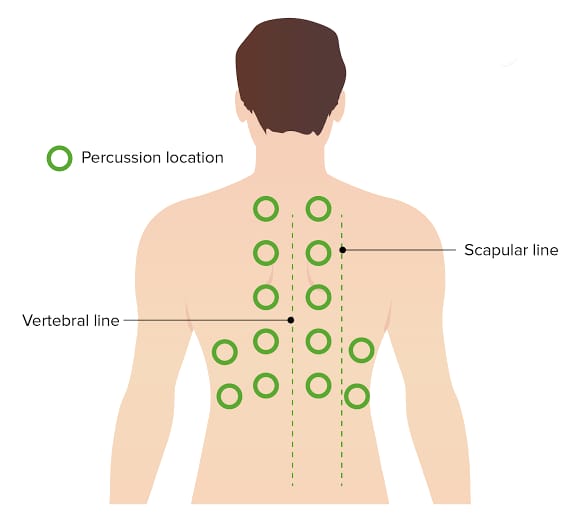

Percussion (પરકશન):

- રેસ્પાયરેટરી પરકશનમાં ચેસ્ટનું ટેપિંગ કરીને અન્ડરલાઇંગ સ્ટ્રકચરને અસેસ કરવામાં આવે છે જેથી ત્યાં એર, ફ્લુઇડ અથવા સોલીડ પ્રેઝન્ટ છે કે નહિ ચેક કરી શકાય.

- જેમાં એન્ટેરીઅર અને પોસ્ટેરીઅર ચેસ્ટને સાઇડ ટુ સાઇડ અને ટોપ ટુ બોટ્ટમ ટેપિંગ કરવામાં આવે છે અને તેના દ્વારા સાંભળવાં મળતા સાઉન્ડને નોટ કરવામાં આવે છે.

- આ ઉપરાંત રેસ્પાયરેટરી પરકશનમાં રેસ્પાયરેટરી એક્સકરસન નોટ કરવામાં આવે છે.

- રેસ્પાયરેટરી પરકશન એ લંગ ડેન્સિટીમાં જોવા મળતા ચેન્જીસને આઇડેન્ટીફાય કરવા તેમજ ન્યુમોનિયા, પ્લુરલ ઇફ્યુઝન જેવી કન્ડીશનને ડાયગ્નોસીસ કરવા માટે ઉપયોગી છે.